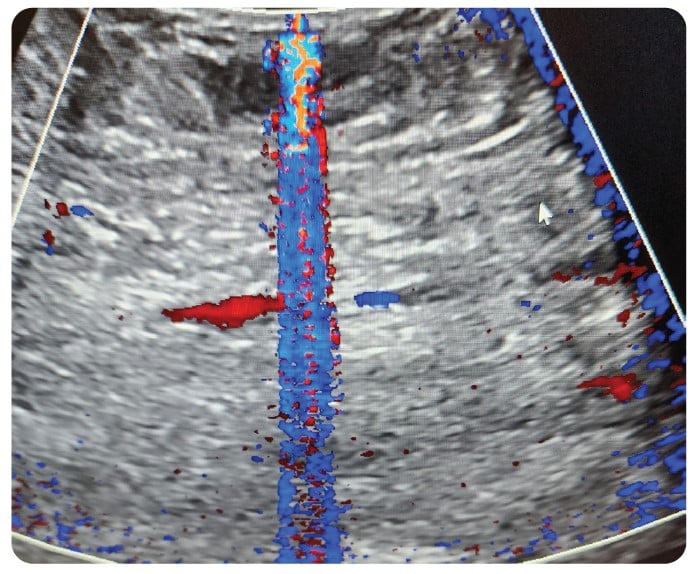

With the proliferation of IoT and wireless technology, the health care setting is even more densely saturated with electronic pollution. Throughout my 30-plus year career in ultrasound, one of the most frequent and most challenging problems to solve has been related to noise artifacts being displayed in an ultrasound image. Typically, these present as axial bands of constant or flashing color in Color Doppler mode. Intense sources of noise can affect 2D imaging in the form of faint gray, semi-axial streaks and/or semi-circular swirls overlaid on the image.